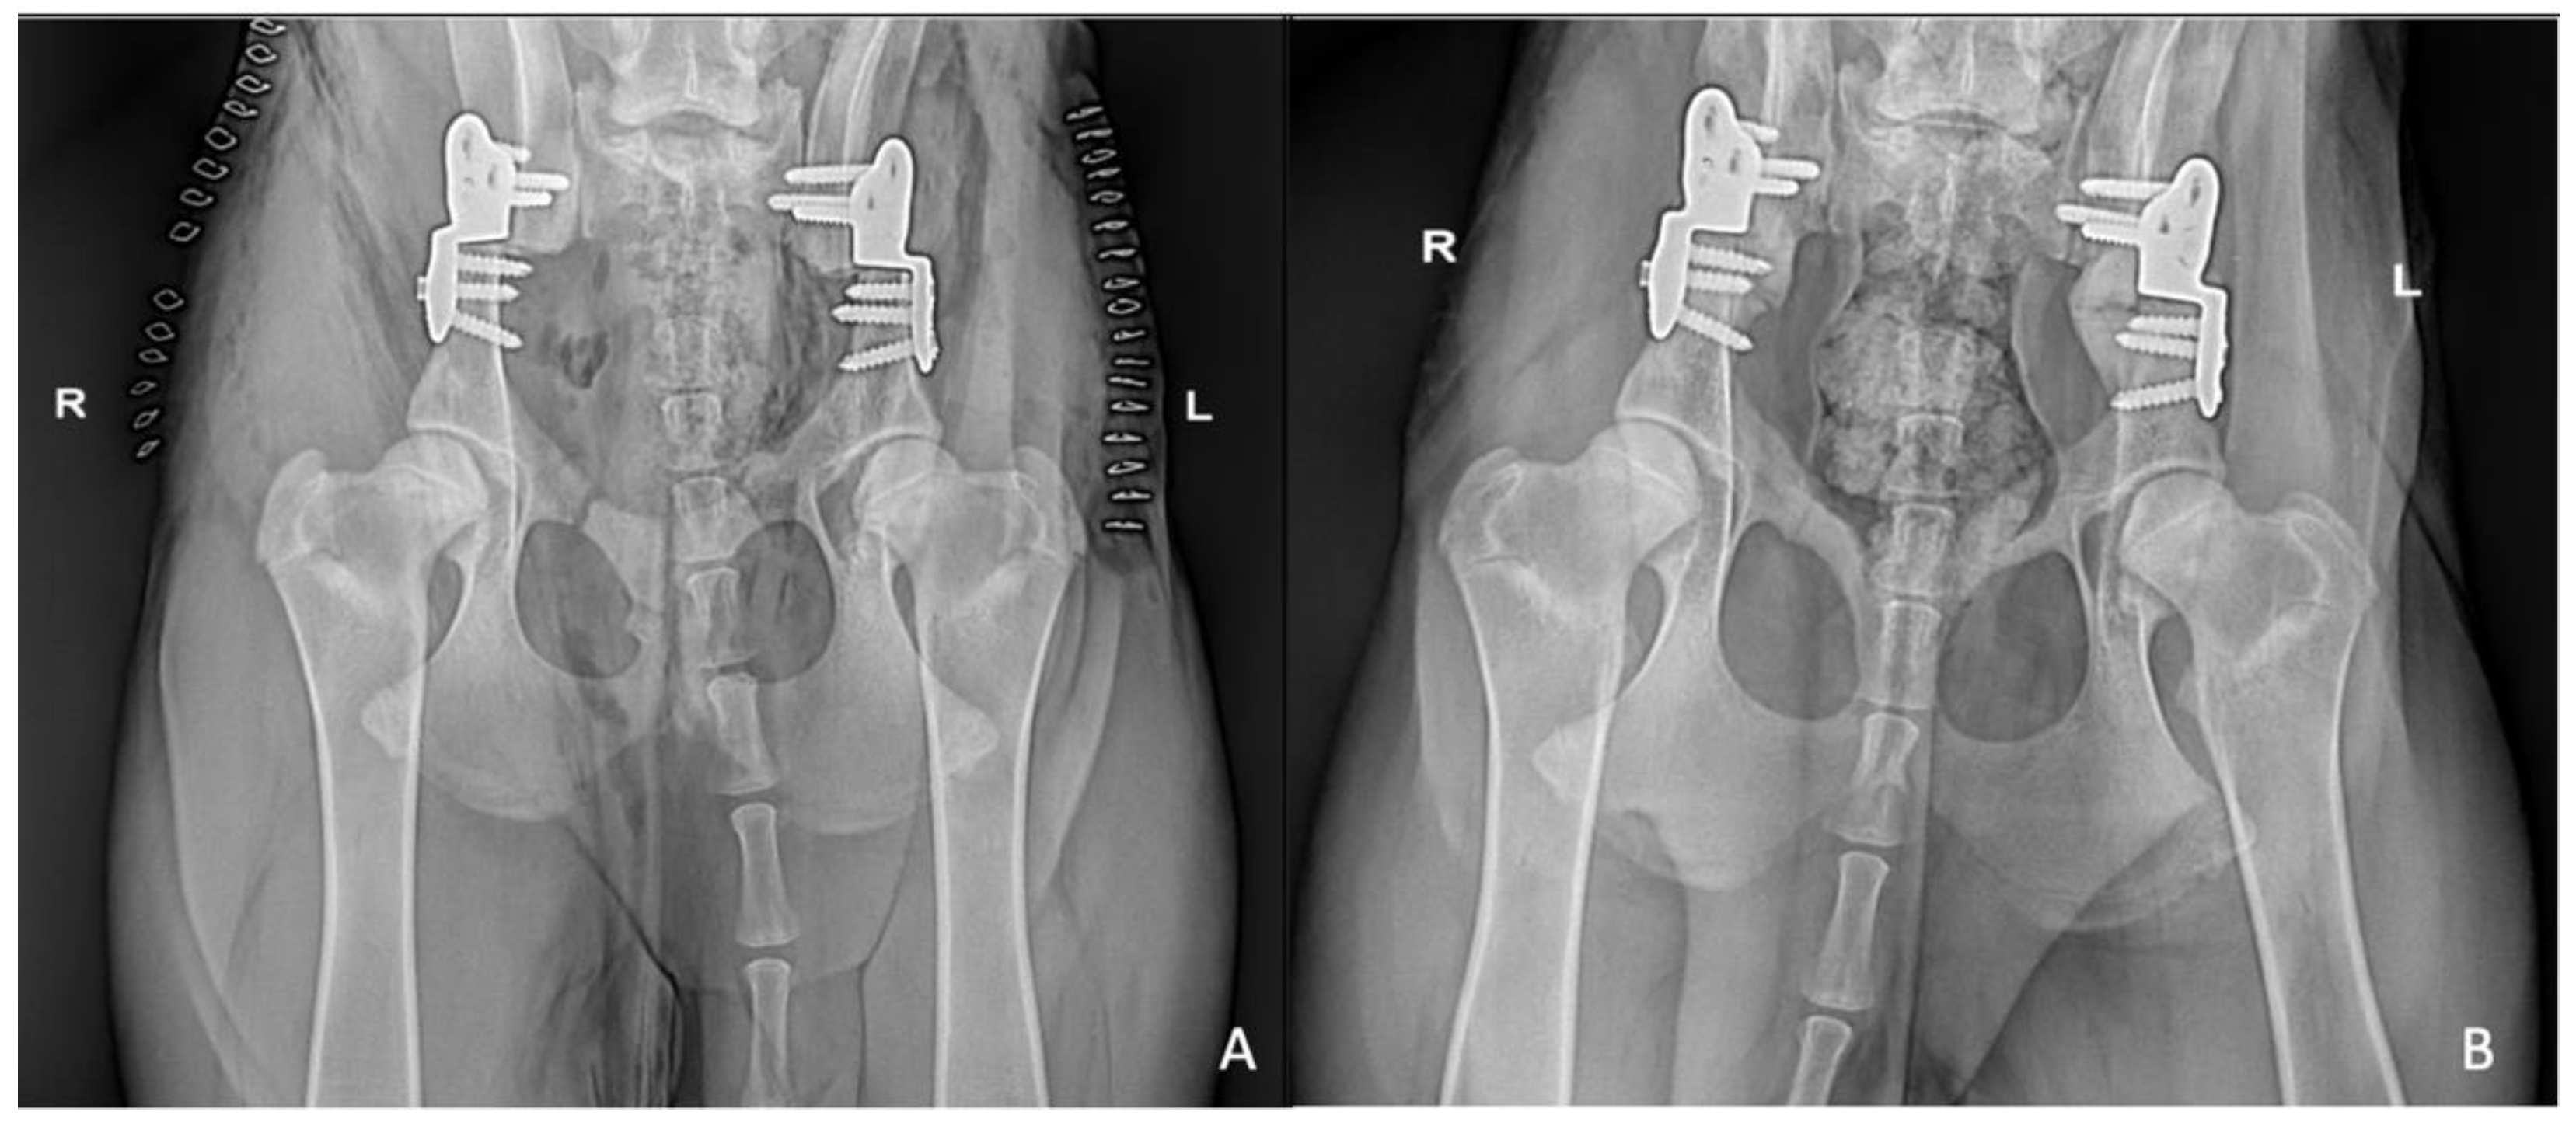

2. Materials and Methods

3. Results